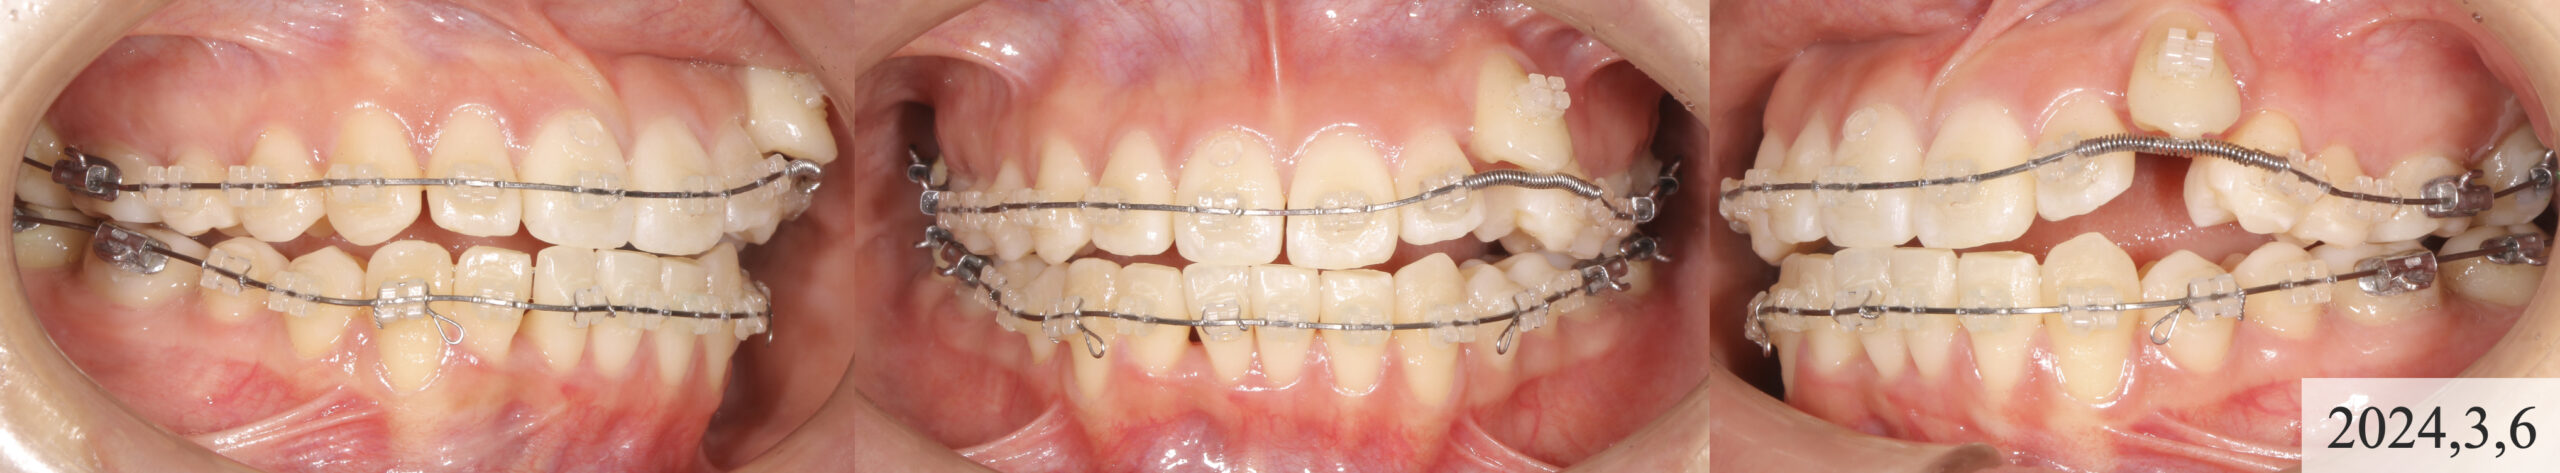

患者様の前歯部は叢生の程度が強く、歯列が舌側に倒れ込んでおらず、犬歯を収めるスペースが不足していました。しかし、パノラマ写真から歯軸が近心に傾斜していることが確認できたため、臼歯群のアップライトを行い、さらに歯のサイズが平均より大きいことを考慮し、顔貌との調和を図る形態へとIPRを施すことでスペースを確保する方針としました。

治療の手順として、まず通常通りレベリングを行い、歯列のフラット化を進めます。その後、ゴムメタルワイヤー(GUMMETAL)が適用可能な段階でワイヤーを変更し、臼歯部のアップライトを行いながらスペースを獲得し、犬歯のためのスペースを確保します。最終的に、咬合と歯列を整えてフィニッシュへと移行する計画としました。

約8ヶ月の治療により、叢生が大幅に改善され、八重歯も適切な位置へと誘導することができました。非抜歯での治療であったため、スペースの確保が課題となりましたが、計画的なアプローチにより対応することができました。その結果、セファロ分析上では前歯がやや唇側に傾斜しましたが、顔貌写真の評価では審美的な問題は認められませんでした。

また、咬合も左右でしっかりと噛み合い、犬歯による顎の誘導も適切に機能しています。患者様からも「自信を持って笑えるようになった」とご満足いただき、治療の成果を実感されていました。

一方で、左側の犬歯については、もう少し舌側へ移動させることで審美性の向上が期待できましたが、患者様のご希望によりこの段階で矯正治療を終了しました。また、犬歯の牽引による歯肉退縮や、叢生による下顎前歯部のブラックトライアングルが認められるため、今後は定期的なメンテナンスを行いながら慎重に経過を観察していきます。